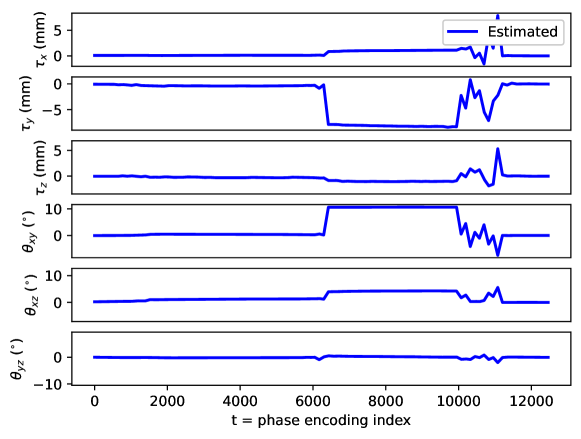

Appendix C Motion parameter estimation

The proposed motion correction algorithm described in Section 2 estimates the rigid motion that the object of interest undergoes during the scan, in order to undo its effect on the reconstructed 3D image. In 3D, the rigid motion is performed by: a plane rotation in the corresponding plane , a plane rotation in the plane, a plane rotation in the plane, a translation in the direction, a translation in the direction, and a translation in the direction (in this order). We adopt the following convention: the direction corresponds to the left-right direction, to the posterior-anterior direction, and to the inferior-superior direction, the plane corresponds to the axial plane, to the coronal plane, and to the sagittal plane. Left/right, anterior/posterior, and inferior/superior are meant from the patient perspective. The orientation of the rotation planes is determined by the right-hand rule.

By design, the prospectively-induced motion for all the experiments detailed in Section 3 follows a step-wise behavior (each step corresponding to a change of pose). In this appendix, we gather the estimated rigid motion parameters for the results shown in Section 4, as a function of time. As noted in the main body of the paper, time is equated to the phase-encoding plane coordinate index, ordered by the corresponding acquisition ordering. We display the estimated motion parameters in Figure 19 (see Sections 3.1, 4.1, Figure 2), Figure 20 (see Sections 3.1, 4.1, Figure 4), Figure 21 (see Sections 3.1, 4.1, Figure 6), Figure 22 (see Sections 3.2, 4.2, Figure 10), Figure 23 (see Sections 3.3, 4.3, Figure 12), and Figure 24 (see Sections 3.3, 4.3, Figure 14).